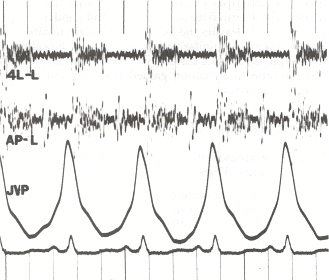

폐고혈압의 다른 전형적인 징후로는 제2심음의 폐 구성 요소 강조, 우심실 제3심음, 흉골 연접 융기(우심실 비대를 나타냄)가 있다. 우심 부전으로 인한 전신 울혈의 징후로는 경정맥압 상승, 복수, 간-경정맥 반사가 있다.[12][13][16] 삼첨판 폐쇄 부전 및 폐동맥판 역류 유무도 확인하며, 이는 폐고혈압과 관련이 있을 수 있다.[12][13][17]